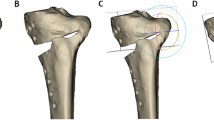

To analyze the effects of the SPOI on the PTS, a square column model with a 10° posterior slope was produced (Fig. 1). A 10° posterior slope was set based on the average value previously reported [11]. Using this square column model, virtual surgery was performed, and the changes were measured.

Autodesk® Maya® software (Autodesk, San Jose, CA, USA) and Rhinoceros® software (McNeel, Seattle, WA, USA) were used for the virtual simulations. The accuracy of these software programs as tools for 3D modeling and simulation has been verified in many medical studies [12,13,14]. The simulation was conducted as follows. First, a virtual square column model with a 10° posterior slope was produced. Second, the SPOI was divided into four types: ① SPOI 20° (posterior-inclined 10° osteotomy), ② SPOI 10° (osteotomy parallel to posterior slope), ③ SPOI 0° (anterior-inclined 10° osteotomy), and ④ SPOI − 10° (anterior-inclined 20° osteotomy) (Fig. 1). A complete posterior cut and true lateral hinge position were applied in the simulation. A true lateral hinge position refers to a hinge position that is parallel to the osteotomy line in the axial view, and complete cutting on the square column model creates a true lateral hinge. The correction angle was increased at 5° intervals from 0° to 30°. The change in posterior slope was measured in the sagittal plane.